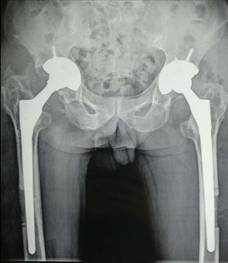

全髋关节置换术治疗股骨头坏死

优点:手术成熟,疗效确切。

术前术后对比

全髋关节翻修术